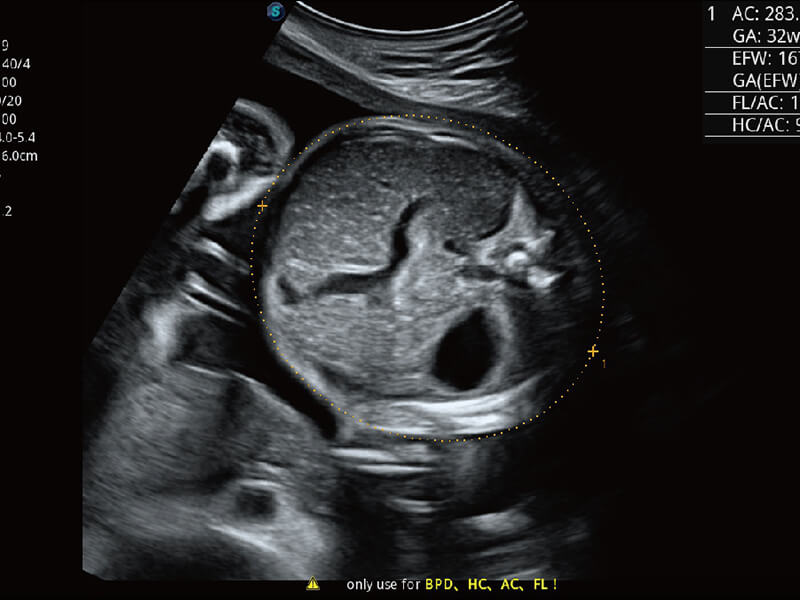

S-Fetus 产科扫查助手

• 缩短

操作时间

• 提升

准确率

• 单次

按键操作